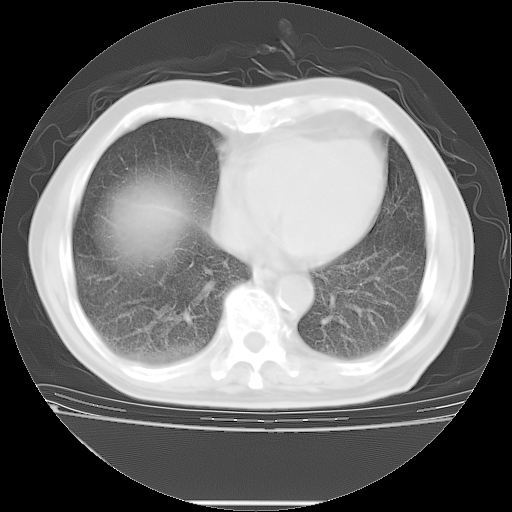

胸腹部CT,诊断意见:左上肺叶钙化灶、左侧胸膜局限性增厚并钙化、胆囊炎。描述部分肺组织呈磨玻璃样改变。